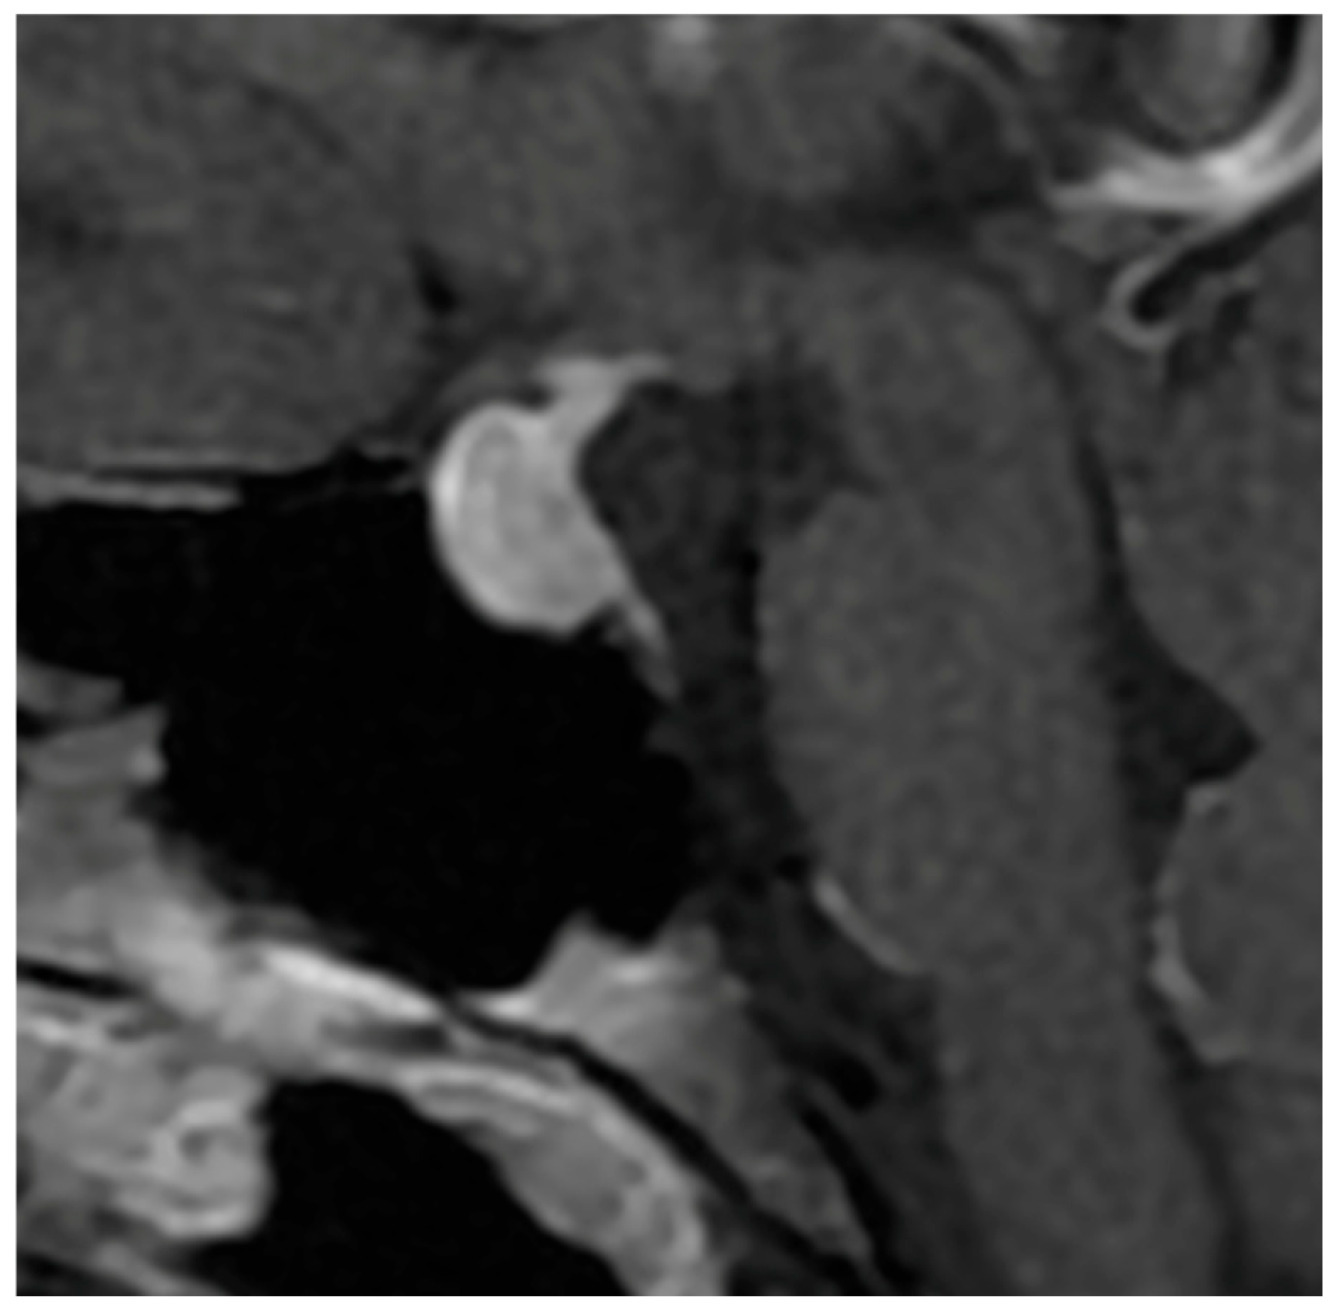

The pattern of enhancement after gadolinium injection provides an additional and highly informative contrast between both entities. Hypophysitis typically demonstrates an intense and homogeneous enhancement, reflecting diffuse vascularized inflammation, with reported rates of homogeneity ranging from 70% to 90% [37,73,74]. NFPMA characteristically show a heterogeneous and often delayed enhancement [75,76,77]. The use of early dynamic post-contrast sequences has been advocated by several authors, as it increases sensitivity for detecting subtle differences in enhancement kinetics between infiltrative and neoplastic processes (Figure 3) [78].

Figure 3. Coronal T1-weighted image after Gadolinium administration showing a NFPMA displacing the normal residual pituitary tissue leftward, which enhances homogeneously and intensely.